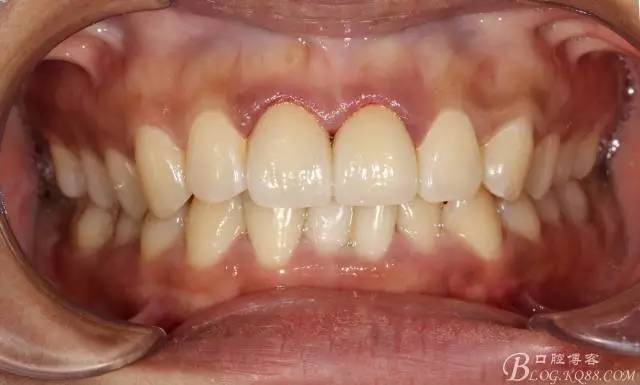

半年后(2016.9)復(fù)查照(這次復(fù)查已完全適應(yīng)修復(fù)后的效果,冷熱也不敏感了,我的心也就放下了)

修復(fù)前后效果對(duì)比照片(看前面的吧)